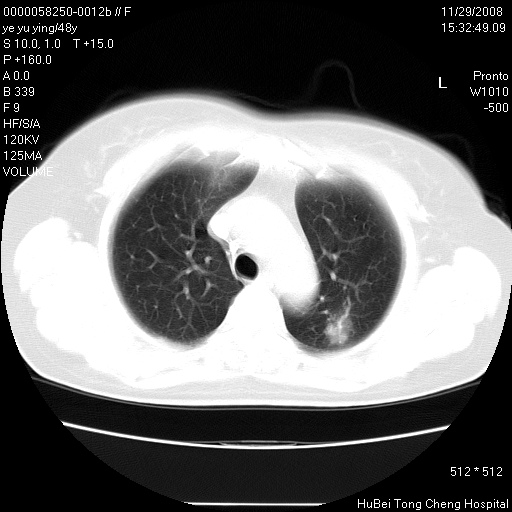

以下是引用huenhao在2008-11-29 22:11:00的发言:[br]脂肪肝,胆囊结石。左肺病灶建议定期复查。

以下是引用liuyue在2008-11-30 5:44:00的发言:[br]1.左肺病变,首先考虑感染性病变,转移待排;建议治疗后复查。[br]2.肝脏密度普遍减低,考虑与化疗有关。[br]3.胆囊结石.